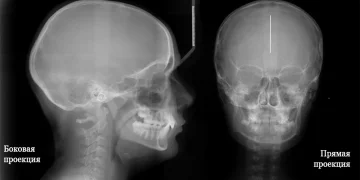

- Рентген головы — это рентгенологическое исследование, позволяющее оценить состояние костей черепа и мягких тканей.

Если целью рентгена головы является диагностика и выявление проблем, то рекомендуется делать обзорный снимок. Когда диагноз уже поставлен и требуется детальное изучение конкретной области черепа, потребуется прицельный снимок.

Одним из ключевых факторов при интерпретации рентгенограмм является правильная техника выполнения исследования. Лишь при соблюдении всех протоколов я могу гарантировать высокое качество снимков, что существенно облегчает процесс диагностики. Я обращаю внимание на такие нюансы, как выбор нужной проекции и положение пациента, поскольку это напрямую влияет на достоверность полученных данных.

Для обеспечения точности результатов во время исследования необходимо полностью зафиксировать голову на короткий срок, не превышающий нескольких минут. Для этого используются специальные повязки и крепления, а также может применяться специальный мешочек с песком. Процедура совершенно безболезненна и оказывает минимальное воздействие на организм. Для повышения точности в установлении диагноза рентгенография головы может проводиться под разными углами.